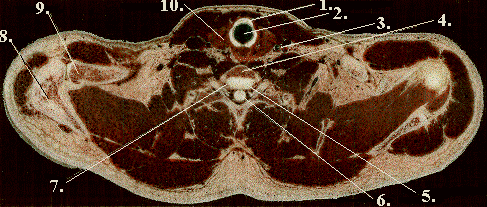

1. Cricoid Caartilage

2. Trachea

3. Common Carotid

4. C-7

5. Intervertebral disc, C-7 & T-1

6. Spinal Chord

7. T-1

8. Scapula

9. Clavicle

10. Thyroid Gland